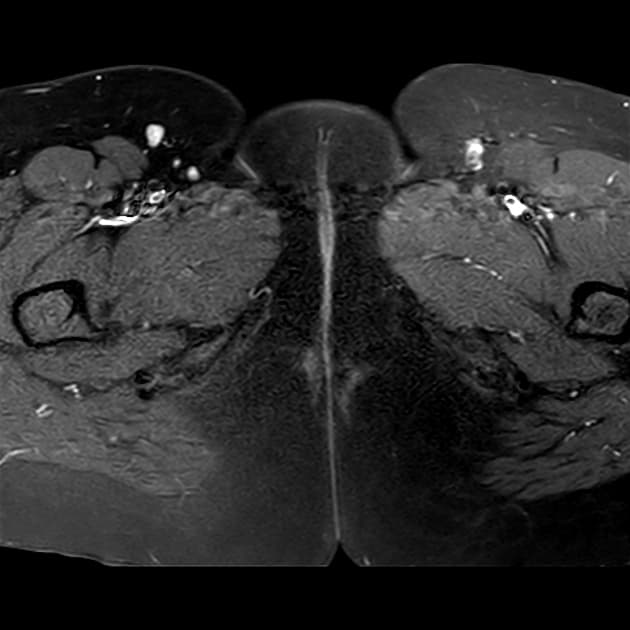

Torus uterinus dày lên, với nhiều ổ xuất huyết ở vùng phụ tạng hai bên, dọc theo mặt sau tử cung và vùng trước trực tràng.

Dày lên trên cộng hưởng từ T2 có tín hiệu giảm (T2 hypointense thickening) ở phần gần và phần giữa dây chằng tử cung cùng (uterosacral ligaments) hai bên.

Tăng sinh mạch máu vùng quanh tử cung (increased parametrial vascularity).